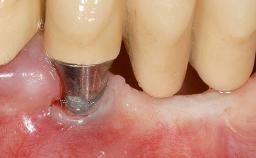

It is sometimes necessary to remove and replace compromised implants. This case is a clear example of the need for multiple steps to achieve an optimal therapeutic result for patients with non-salvageable implants. It illustrates how the lost soft and hard tissues were rebuilt in a sequence that improved the healing of the hard tissues and assured their long-term stability. The 35-year-old healthy patient presented with clinical attachment loss on the proximal and lingual surfaces of the natural dentition. Some gingival recession was present on natural teeth, particularly in the posterior sextants (S1, S3, S4, and S6).